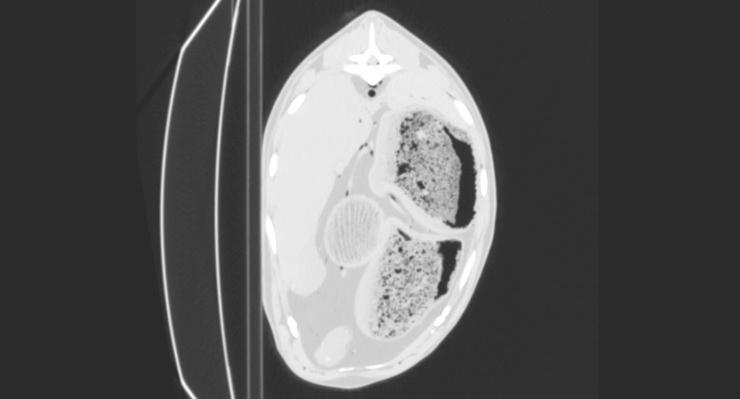

Evaluation of the usefulness of air as a negative contrast medium of blood vessels in goats in post mortem computed tomography (PMCT) and establishing the protocol with appropriate doses and timing of the contrast medium administration.

Thirty three goats were euthanized 10 to 300 min before the study. First, in 3 goats air was administered into the left or right common carotid artery at dose of 60, 100 and 120 ml/kg, and after each dose PMCT was performed in lateral recumbency. As the latter dose proved to visualize blood vessels best, following 30 goats were examined in the same manner but only with the use of air dose of 120 ml/kg. The quality of CT scans was evaluated independently by two board-certified radiologists.

RESULTS

In all studied animals the vascular system filled with air was clearly visualized on CT scans. In most of goats this amount of air revealed vessels smaller than 4 mm in diameter.

评估空气作为死后计算机断层扫描(PMCT)中血管负性对比介质的用途,并制定合适剂量和对比介质给药时间的方案。

33 只山羊在研究前 10 至 300 分钟被安乐死。首先,在 3 只山羊中,以 60、100 和 120 ml/kg 的剂量将空气注入左或右颈总动脉,每次给药后在侧卧位进行 PMCT。由于后一个剂量证明可以最好地显示血管,随后对 30 只山羊以相同的方式进行检查,但仅使用 120 ml/kg 的空气剂量。两名经过委员会认证的放射科医生独立评估 CT 扫描的质量。

结果

在所有研究动物中,血管系统都在 CT 扫描中清晰可见。在大多数山羊中,这种数量的空气揭示了直径小于 4 毫米的血管。